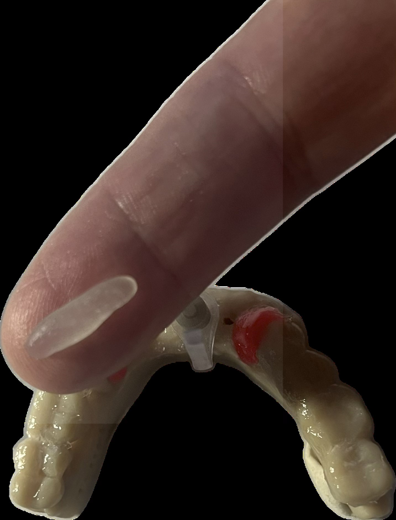

Paste placed around the guide sleeve, then on the ridge and occlusal surface of the teeth

Surgical guide after polymerization of the paste

Ready-to-use surgical guide.